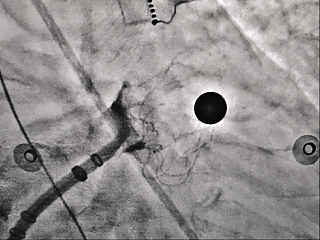

展开封堵器后牵拉试验并造影

牵拉试验

封堵器顺应心耳形态,稳定锚定

多切面造影确认,封堵完全,无残余分流